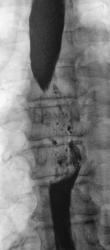

Линейные томограммы в прямой проекции

По представленным снимкам, у меня сложилось впечатление что пищевод как бы сдавлен извне (овал), возможно образованием в заднем средостении; при этом на довольно продолжительном участке есть нарушение архитектоники складок слизистой с множественными участками barium depletion (стрелки), свидетельствующими в пользу изъязвления.

Исходя из вышесказанного, по данному случаю: сдавление просвета и смещение пищевода мягкотканным образованием, выходяшим за пределы стенки, изъязвление передней стенки пищевода. Заключение: подслизистая опухоль пищевода с изъязвлением, вероятнее всего лейомиома. Рекомендации: эндоУЗИ с биопсией, КТ.

После проведенного рентгенологического исследования органов грудной полости - рентгенографии и томографии, при которой были выявлены увеличенные лимфатические узлы в корнях лёгких и средостении, было проведено рентгенотелевидение пищевода с прицельной рентгенографией и исследованием пищевода на трохоскопе, с контрастированием пищевода водной взвесью сернокислого бария "различной консистенции" - от сверхжидкого - до пастообразного, для "выяснения состояния" заднего средостения. Была зарегистрирована и документирована "локальная деформация пищевода" на протяжении 9,5 см. с перестройкой структуры "рельфа слизистой оболочки".